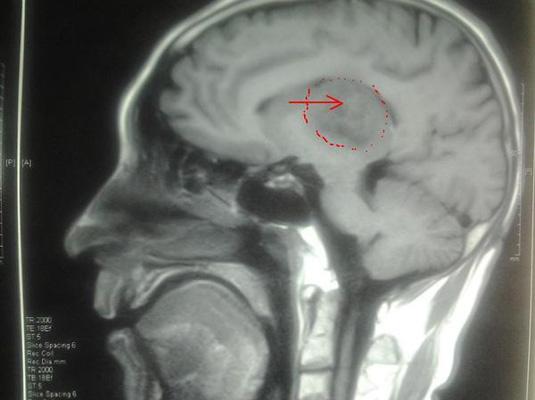

随着放疗设备的不断进步,现在我们所使用的设备有多挡电子线质(4Mev、6 Mev、9 Mev、12 Mev、16 Mev、20 Mev)和光子线能量(6 Mv、10 Mv、15 Mv),也就是说,对于全身不同深度的肿瘤我们能够得心应手的使用不同级别的能量进行治疗,无论肿瘤君是附着在皮肤表面还是深藏在大脑之中还是肺腑当中,我们都能够准确的把它干掉。